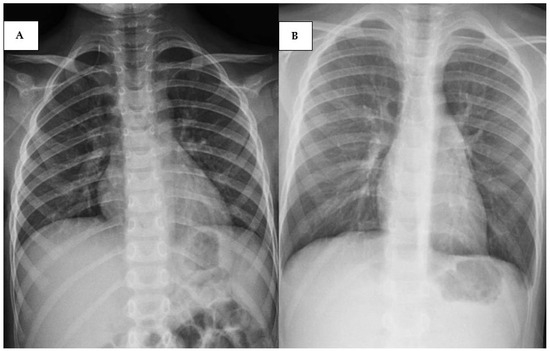

2.3. Cases 3 (UPN 1076952) and 4 (UPN 1077940)